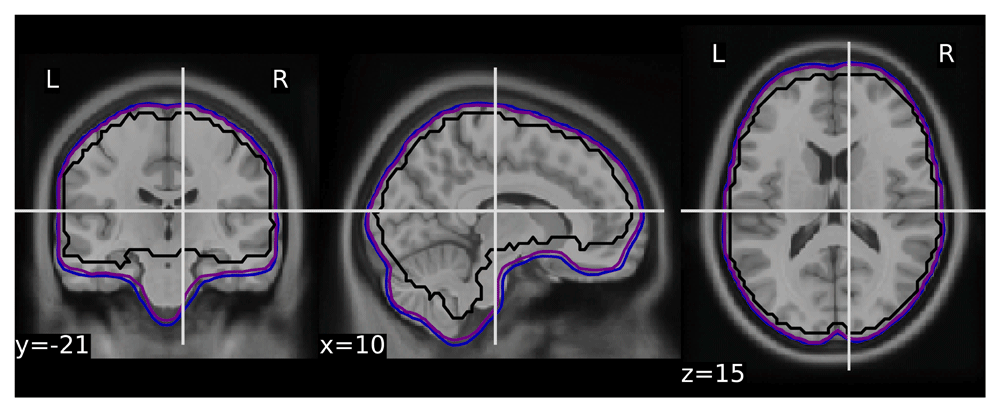

To validate the quality of volumetric spatial normalization we have looked at the overlap of the EPI derived brain masks in the MNI space (across all participants and runs - total of 1,969 masks - see Figure 1). The within subject coregistration and normalization worked well for the vast majority of participants, creating a very good overlap. All of the issues observed while processing the dataset are listed in Table 1.